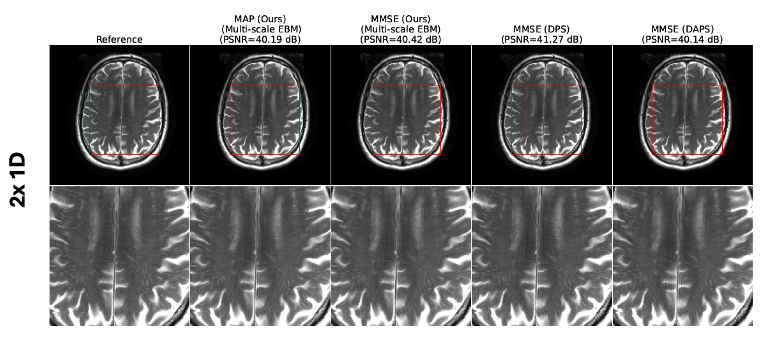

4.2.2 MRI image reconstruction

We evaluate multi-scale EBMs for MRI reconstruction from undersampled measurements at two acceleration factors. EBMs were distilled from the diffusion model in [1] using a T2-weighted brain dataset of 40,442 slices and tested on 40 slices. We compare against two diffusion-based algorithms: (a) DPS and (b) DAPS. We use the same noise scheduler as in the previous example (, , ), Langevin steps, and iterations. MMSE and uncertainty are estimated from five samples; MAP is computed via Algorithm 1 over iterations. Table 3 shows EBMs achieve performance comparable to DAPS for both accelerations. Fig. 4(a,b) illustrates reconstructions at 4× and 8×. Unlike diffusion models, EBMs provide MAP estimates without multiple samples, reducing inference cost and enabling practical clinical deployment.